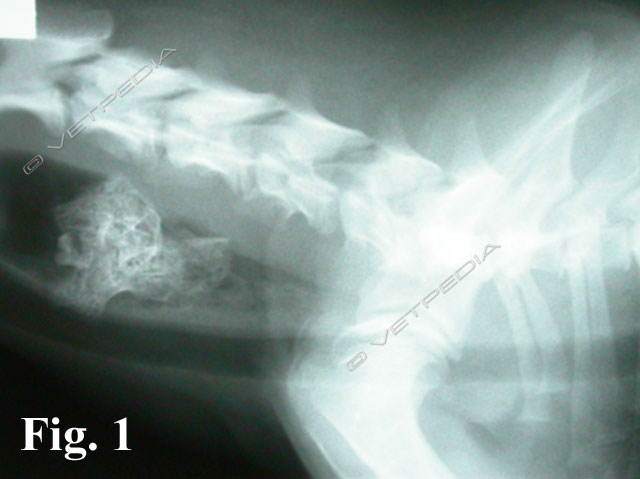

La misurazione dell’ormone adrenocorticotropo (ACTH) endogeno rappresenta un test di laboratorio utile per valutare la funzionalità dell’asse ipotalamo-ipofisi-surrene (HPA) (Fig. 1) qualora si sospetti una patologia endocrina di origine ipofisaria o surrenalica. L’ACTH è un ormone estremamente labile e sensibile alle alte temperature e p...